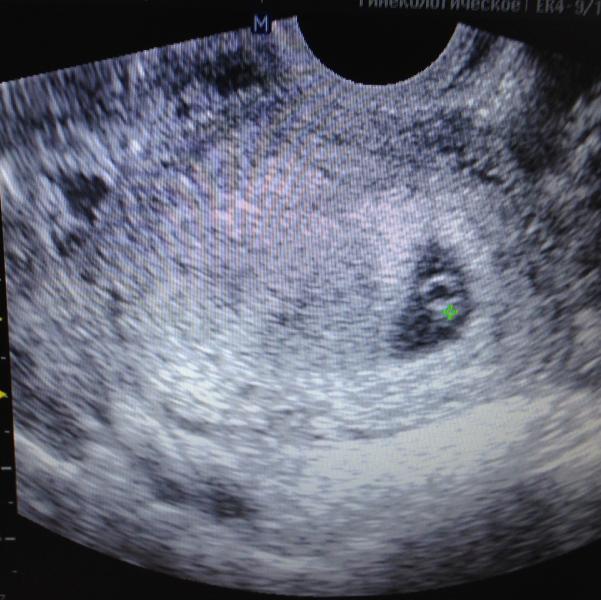

Вот и появился на УЗИ мой крошечка))) Так волнительно было ожидание, тест еще 2 недели назад показал две полоски.

@marikam, я и не сомневалась что вы про ПЯ)))))) а ктр или как там его, у нас было 12мм.

@natusik_juicy, я досмотрела крт 8 мм, плодное 22мм, у меня просто все в голове перепуталось 😄 Работа, работа, перейди на Федота😃

@marikam, ну вот говорю большой или у меня мелкий))) 7.3 : 22мм было)) я ща переживать начну😕

@natusik_juicy, мне написали вчера в справке узи срок 4,6; 22 мм я считаю по зачатию)))